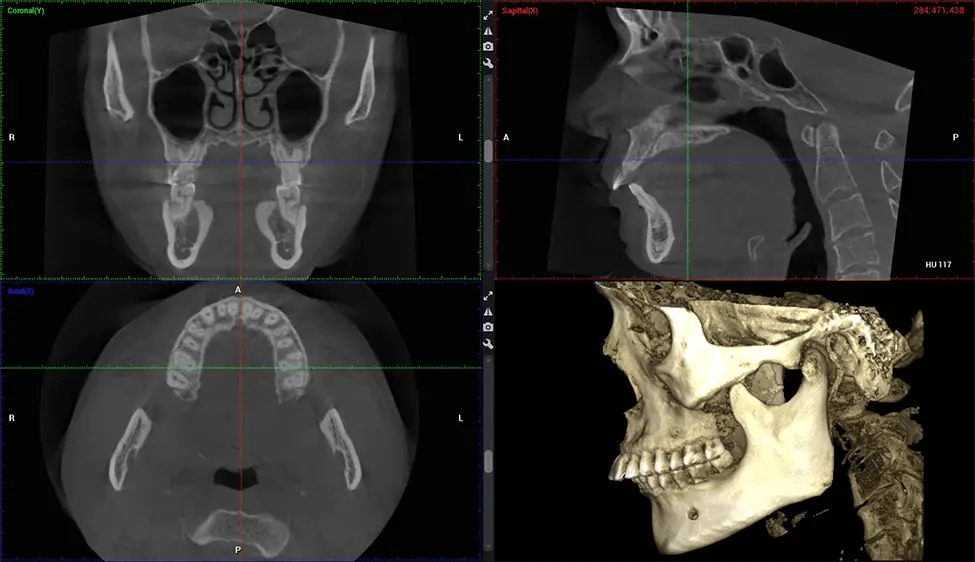

Cone Beam Computed Tomography (CBCT) is an advanced imaging technique used in dentistry and maxillofacial surgery to obtain detailed 3D images of the oral and maxillofacial structures. At Dr G Dental Studio, our CBCT scanners utilize a cone-shaped X-ray beam and a specialized detector to capture images from different angles. A computer then combines these images to create a 3D representation of the patient’s oral anatomy.

This 3D scan, called cone beam computed tomography, gives your dentist a more complete image of your oral anatomy and disease processes than a traditional X-ray. Unlike conventional X-rays, which capture a 2D image of your mouth from various angles, a 3D scan takes multiple digital X-rays for one image. It provides a complete view of your jaw, teeth, nerves, and soft tissues. This enhanced view allows dentists to detect minor issues not visible in traditional 2D scans, such as impacted wisdom teeth or bone fractures in the sinus cavity.

There are many benefits to using CBCT technology, especially compared to the traditional 2D X-ray format. One of the most significant advantages of CBCT scans is that they provide much more information than traditional X-rays. A scan lets your dentist see images from all angles of your jaw and mouth, including your sinuses, nasal cavity, cheekbones, and other surrounding areas. This added information helps your dentist craft a comprehensive treatment plan that addresses all aspects of your oral health.

The patient is first positioned in the CBCT scanner, which typically consists of a rotating arm that houses the X-ray source and a detector. The patient’s head is immobilized to ensure accurate image capture. The X-ray source and detector rotate around the patient’s head, capturing various X-ray images from multiple angles. As the X-ray source rotates, it emits the cone-shaped X-ray beam towards the detector. The detector captures the X-ray images, which are then processed by the CBCT software.

After the scanning process, the captured X-ray images are processed by the CBCT software, which applies algorithms to reconstruct a detailed 3D image of the scanned area. The software compiles these individual X-ray images and creates a digital 3D representation of the patient’s anatomy. The reconstructed 3D CBCT image can be viewed and analyzed by the dentist or radiologist. This image can be manipulated, rotated, and zoomed in or out to examine specific structures and evaluate the patient’s condition.